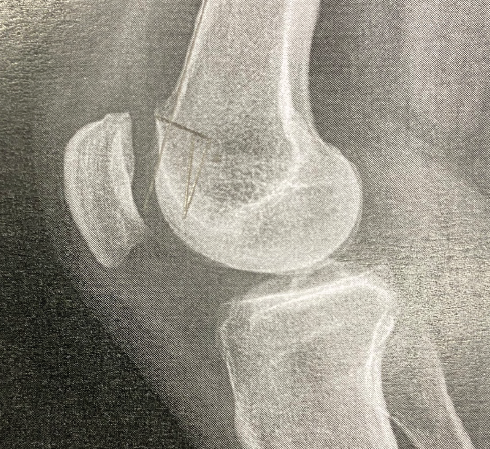

Chondroblastoma of the Right Distal Femur Medial Condyle: A Case Report

Sabare Naaharaaj , Mohammed Tavfiq , J K Giriraj Harshavardhan , Balaji Vijayan

………………………………p.213-218